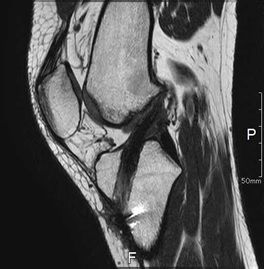

MRI所見

| 手術前 | 手術後 |

| ACLの緊張および連続性は消失している | 再建靱帯の成熟を認める |